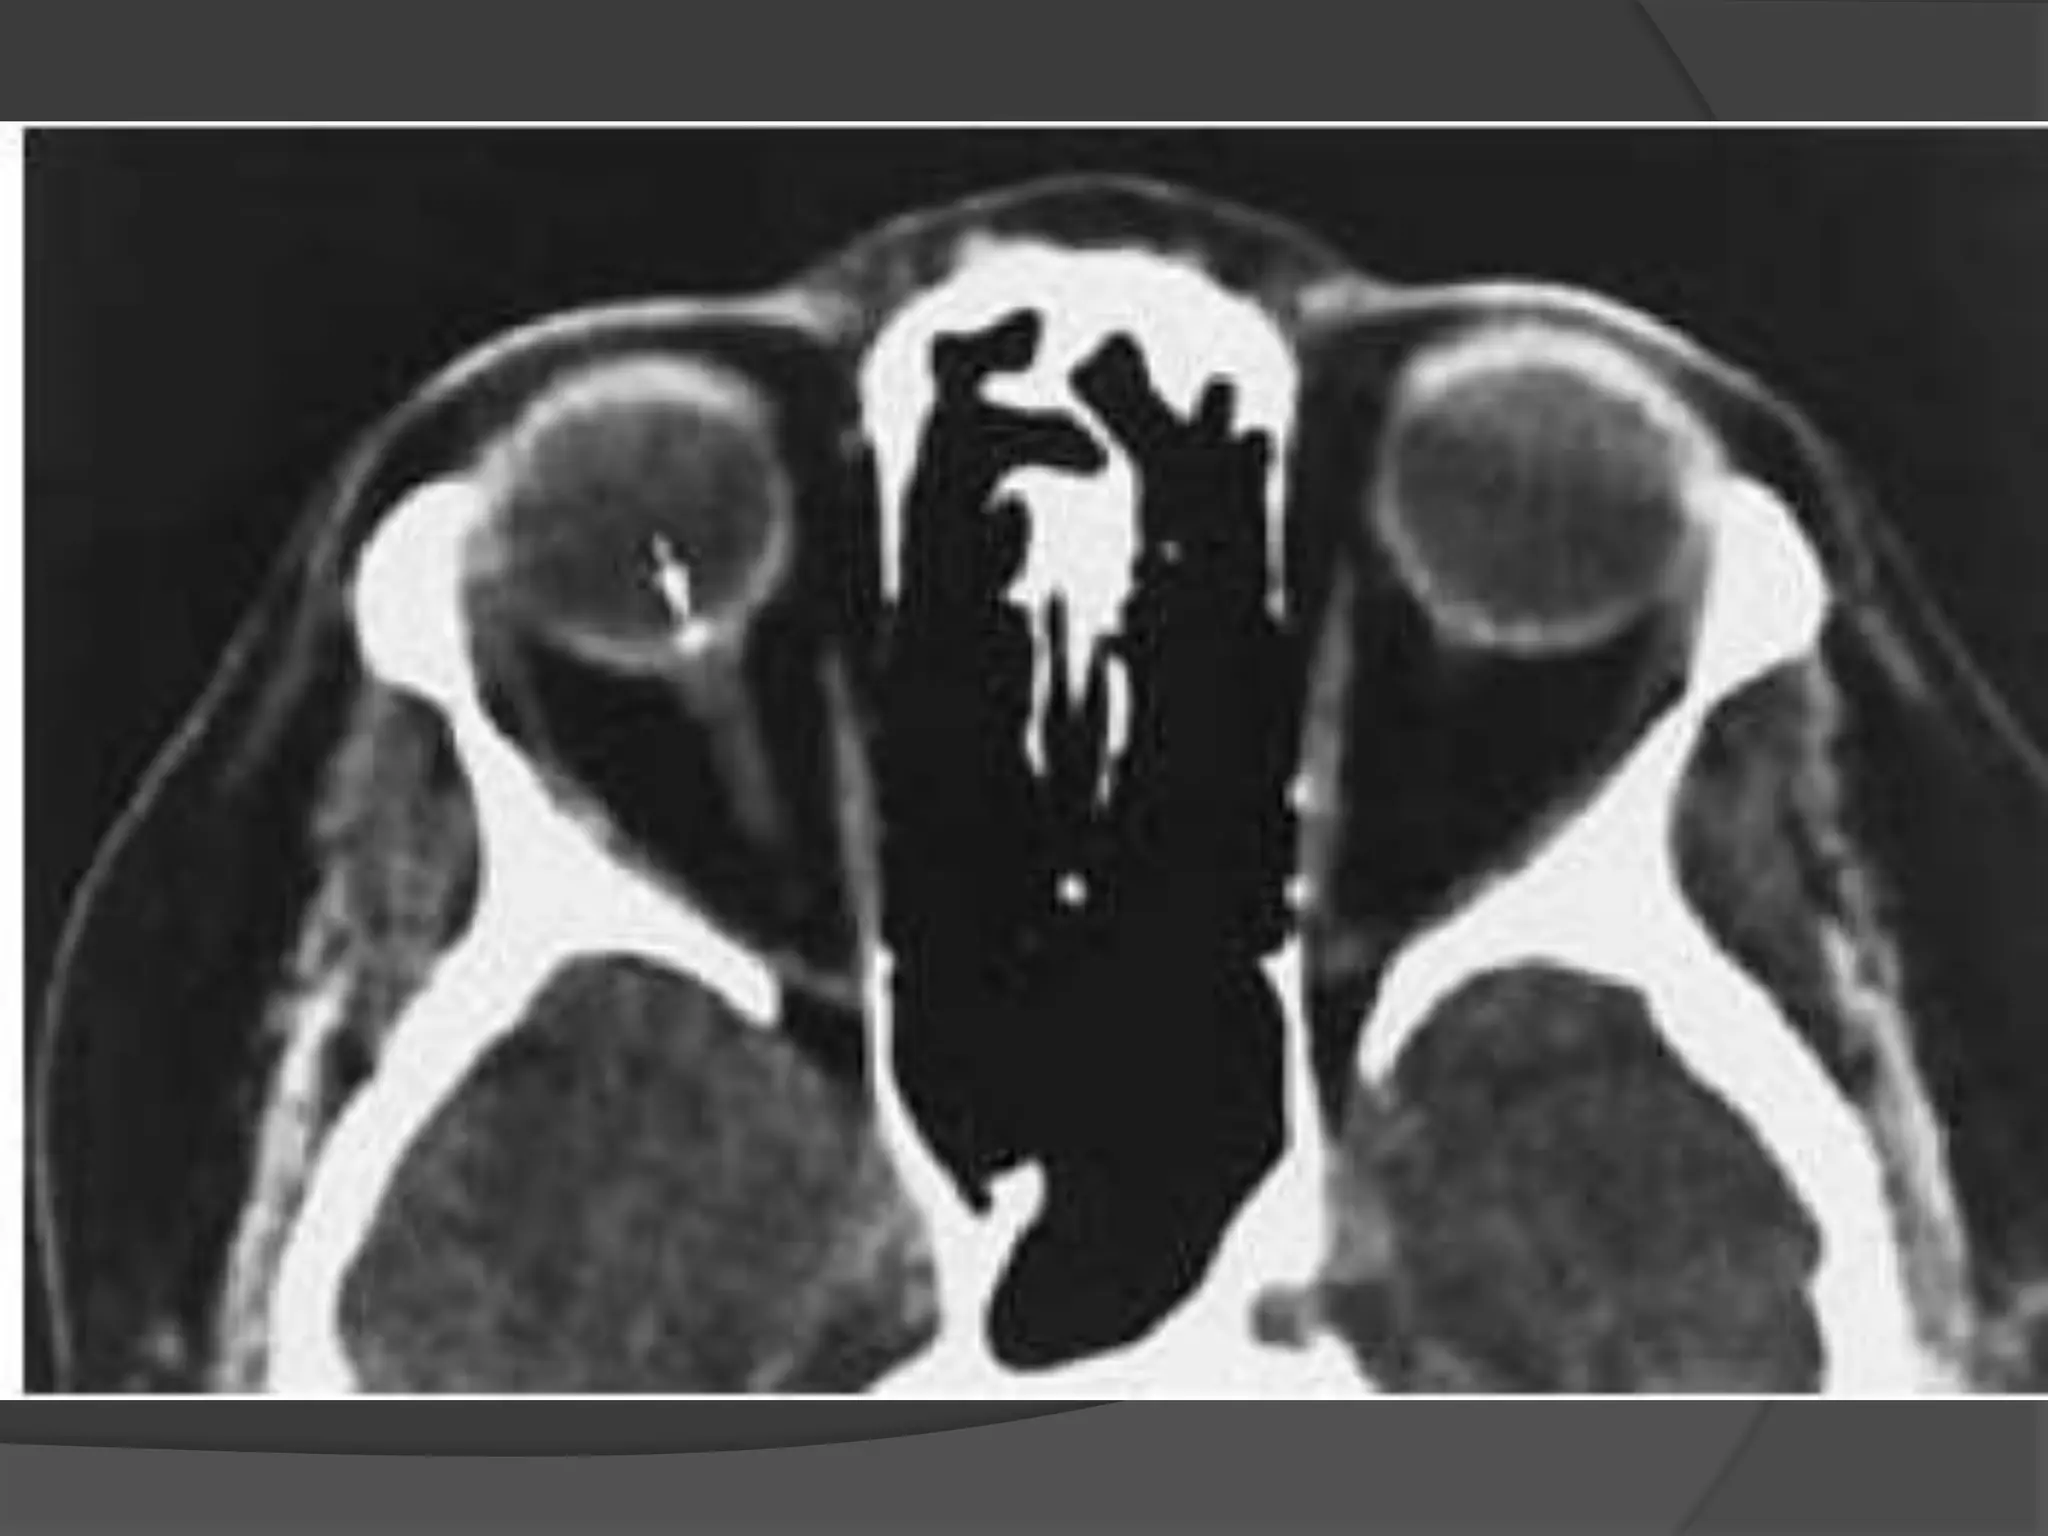

Prostatic Ca: Axial CT (A) shows small lytic lesion of left lateral orbital wall.

Soft-tissue windows (B) demonstrate contiguous extension of soft tissue into

lateral extraconal compartment (asterisk) with medial displacement of the

lateral rectus muscle.